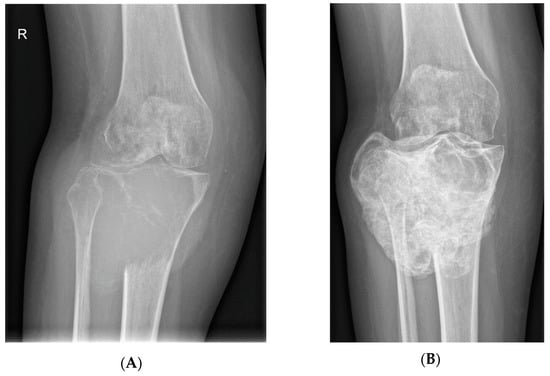

- Van Langevelde, K.; McCarthy, C.L. Radiological findings of denosumab treatment for giant cell tumours of bone. Skelet. Radiol. 2020, 49, 1345–1358. [Google Scholar] [CrossRef] [PubMed]

- Murphey, M.D.; Nomikos, G.C.; Flemming, D.J.; Gannon, F.H.; Temple, H.T.; Kransdorf, M.J. Imaging of Giant Cell Tumor and Giant Cell Reparative Granuloma of Bone: Radiologic-Pathologic Correlation. RadioGraphics 2001, 21, 1283–1309. [Google Scholar] [CrossRef]

- Oguro, S.; Okuda, S.; Sugiura, H.; Matsumoto, S.; Sasaki, A.; Susa, M.; Morioka, H.; Jinzaki, M. Giant Cell Tumors of the Bone: Changes in Image Features after Denosumab Administration. Magn. Reson. Med. Sci. 2018, 17, 325–330. [Google Scholar] [CrossRef]

- Hakozaki, M.; Tajino, T.; Yamada, H.; Hasegawa, O.; Tasaki, K.; Watanabe, K.; Konno, S. Radiological and pathological characteristics of giant cell tumor of bone treated with denosumab. Diagn. Pathol. 2014, 9, 111. [Google Scholar] [CrossRef]

- Branstetter, D.G.; Nelson, S.D.; Manivel, J.C.; Blay, J.-Y.; Chawla, S.; Thomas, D.; Jun, S.; Jacobs, I. Denosumab Induces Tumor Reduction and Bone Formation in Patients with Giant-Cell Tumor of Bone. Clin. Cancer Res. 2012, 18, 4415–4424. [Google Scholar] [CrossRef] [PubMed]